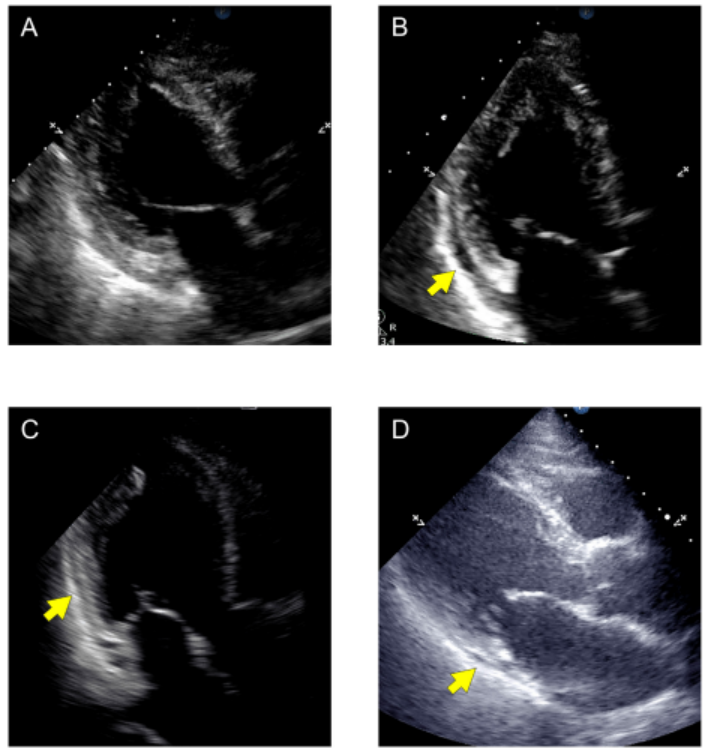

入院后第23天,患者出现左胸疼痛伴高热,体温达39.6℃。前倾位听诊时可闻及心包摩擦声。心电图显示胸前导联ST段弓背向下抬高、PR段压低(图1B)。在进行实验室检查、尿检、CT、心脏超声和冠状动脉造影后,没有发现感染或急性冠状动脉综合征的迹象。但化验提示嗜酸性粒细胞计数升高5.1%(291 cells/mL),心脏超声提示新发心包积液(6 mm)(图2B)。诊断为Dressler综合征,予秋水仙碱0.5 mg/d和对乙酰氨2000 mg/d。患者的体征和实验室指标在几天内有所改善,并于入院后第32天出院。

3个月后,患者心电图ST段抬高恢复正常(图1C),心包积液也有所改善(图2C)。秋水仙碱0.5 mg/d持续治疗6个月,无任何副作用,症状未复发,检查较前无明显变化(图1D,2D)。

图2 入院时(A)、出院后第23天(B)、出院后3个月(C)和6个月(D)进行超声心动图检查。黄色箭头表示心包积液